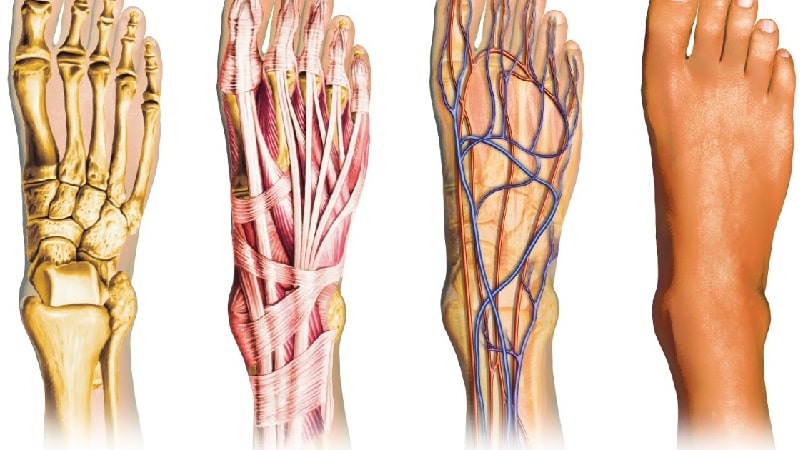

Мышцы

Движение стопы осуществляется за счет мышц, которые находятся на костях голени, а также на тыльной и подошвенной частях ноги. На подошве располагаются три группы мышц, отвечающих за подвижность большого пальца, мизинца и всех остальных пальцев:

- Внутренняя группа: включает в себя мышцу, отводящую большой палец, мышцу, приводящую большой палец, и короткий сгибатель большого пальца. Эти мышцы начинаются от плюсневых и предплюсневых костей и прикрепляются к основанию проксимальной фаланги большого пальца.

- Наружная группа: состоит из мышцы, отводящей мизинец, и короткого сгибателя мизинца. Они прикрепляются к проксимальной фаланге пятого пальца.

- Средняя группа: включает короткий сгибатель пальцев (который прикрепляется к средним фалангам 2-5 пальцев), квадратную мышцу подошвы (крепится к сухожилию длинного сгибателя пальцев), червеобразные мышцы, а также тыльные и подошвенные межкостные мышцы, направленные к проксимальным фалангам 2-5 пальцев. Эти мышцы начинаются на костях предплюсны и плюсны на подошве стопы. Червеобразные мышцы берут начало от сухожилий длинного сгибателя пальцев. Все перечисленные мышцы выполняют функции сгибания, разведения и сведения пальцев стопы.

На тыльной стороне стопы находятся две мышцы — короткий разгибатель пальцев и короткий разгибатель большого пальца. Эти мышцы начинаются от наружной и внутренней поверхности пяточной кости и прикрепляются к проксимальным фалангам пальцев. Их основная функция — разгибание пальцев стопы. Остальные мышцы берут свое начало от костей голени.

Нервы и кровоснабжение

Функционирование стопы невозможно без нервных окончаний, которые передают сигналы в центральную нервную систему, вызывая сокращения мышц. Благодаря иннервации человек способен ощущать боль, прикосновения, а также изменения температуры, такие как холод и тепло.

На стопе располагаются четыре основных нерва:

Кровеносные сосуды идут рука об руку с нервными окончаниями по всему организму. Задняя и передняя большеберцовые артерии обеспечивают кровоснабжение стоп. Они делятся на наружные, внутренние и тыльные артерии на подошве, формируя артериальные соединения. Отток крови осуществляется по тыльной стороне стопы через малые и большие подкожные вены, которые проходят по голени.